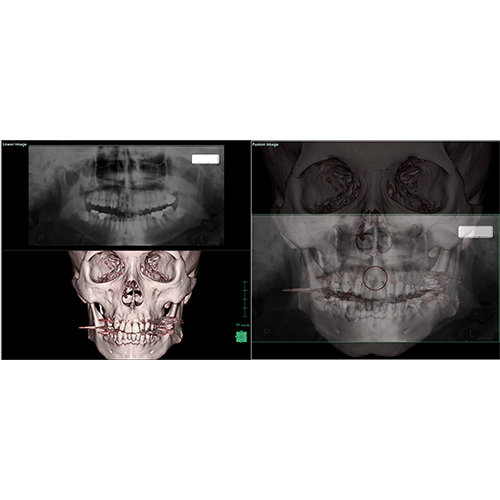

View X-Ray CT & MRI Scans Fast and Easily

Designed for surgeons, Pro Surgical 3D makes it easy to view patient scans quickly. Pro Surgical 3D facilitates the optimal 3D treatment and assessment workflows based on X-ray CT and MRI scans – and best of all, it’s FREE!

High-quality and fast 3D reconstruction and 3D rendering

Performs 3D reconstruction and volume rendering.

Side-by-side comparative assessment for pre- and post-operative scans.